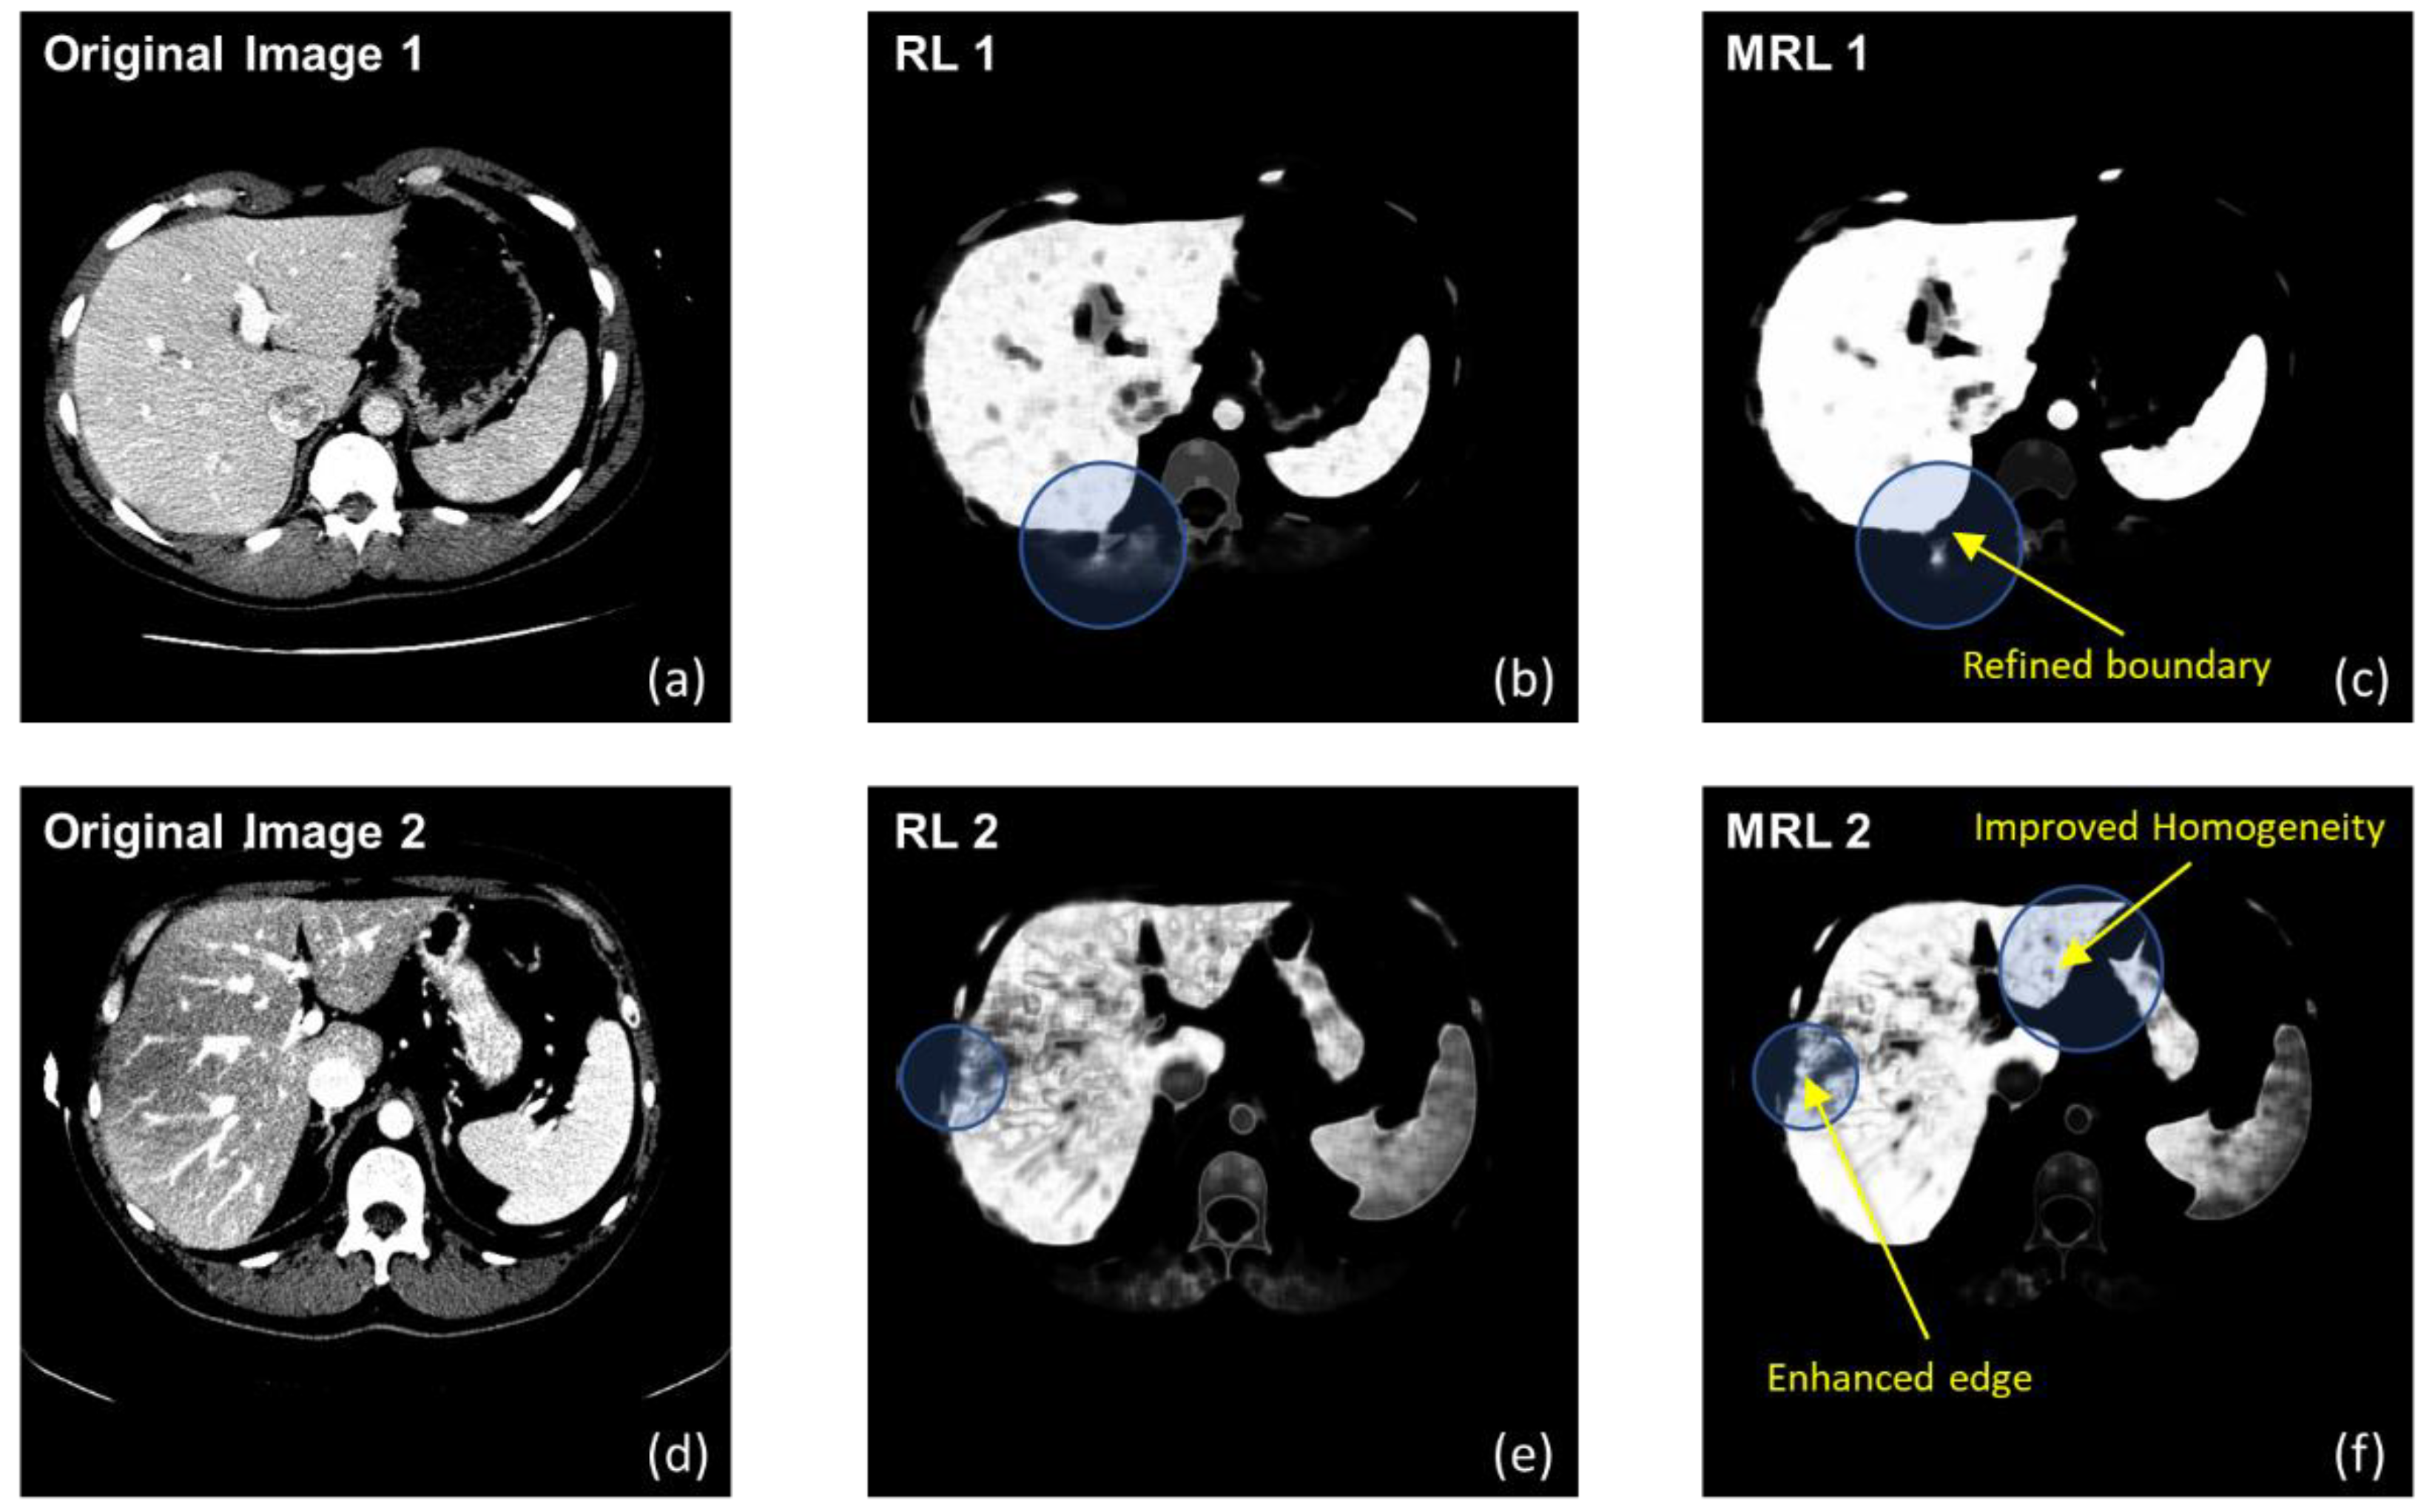

Figure 2 illustrates some soft labeling examples, comparing between results obtained by a non-RL, and homogeneity improvement made by MRL.

It is evident that the liver boundaries are refined, while artifacts are reduced. Unlike other similar works, MRL was used in this study only as preprocessing, and thus definitive binary classification was not fully committed as yet. Therefore, instead of continuing the updates until convergence, these examples were obtained after only five iterations.

Figure 2. Labeling examples of two selected slices (a,d), given by a non-RL (b,e) and MRL (c,f). The circles highlight areas of improvement, which are of a refined boundary and much more homogeneous regions.